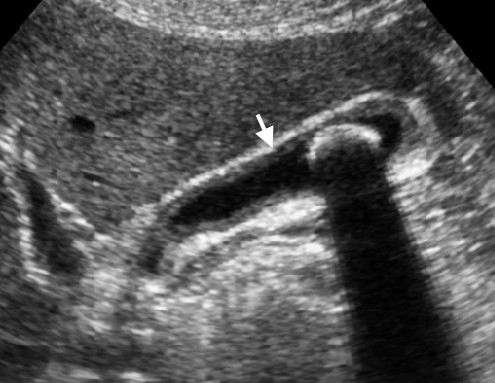

8. kép:

Epekő